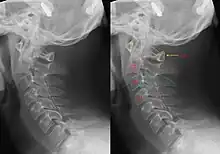

| Hangman's fracture | Hangman | fracture of both pedicles of C2 | distraction and extension of neck | Hangman's fracture Archived 2020-09-18 at the Wayback Machine at Wheeless' Textbook of Orthopaedics online |

|